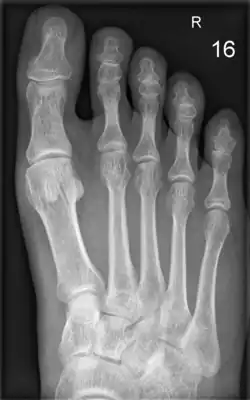

Die Zehenglieder

Die Zehenknochen (Ossa digiti oder Ossa digitorum pedis) ähneln im Aufbau den Fingerknochen. Die große Zehe besitzt zwei Glieder, alle übrigen Zehen sind dreigliedrig. Die Glieder werden in Grundglied (Phalanx proximalis), Mittelglied (Phalanx media) und Endglied (Phalanx distalis oder Phalanx unguicularis) unterteilt. Bei Huftieren werden sie als Fessel-, Kron- und Hufbein bezeichnet. An den Zehenknochen lassen sich die Basis, der Körper und der Kopf unterscheiden.

Die Gelenke zwischen Mittelfußknochen und Grundgliedern werden als Zehengrundgelenke (Metatarsophalangealgelenke) bezeichnet. Das Gelenk zwischen Grund- und Mittelglied trägt die Bezeichnung Mittelgelenk oder proximales Interphalangealgelenk (PIP). Zwischen dem Mittel- und dem Endglied befindet sich das Endgelenk (distales Interphalangealgelenk, DIP).